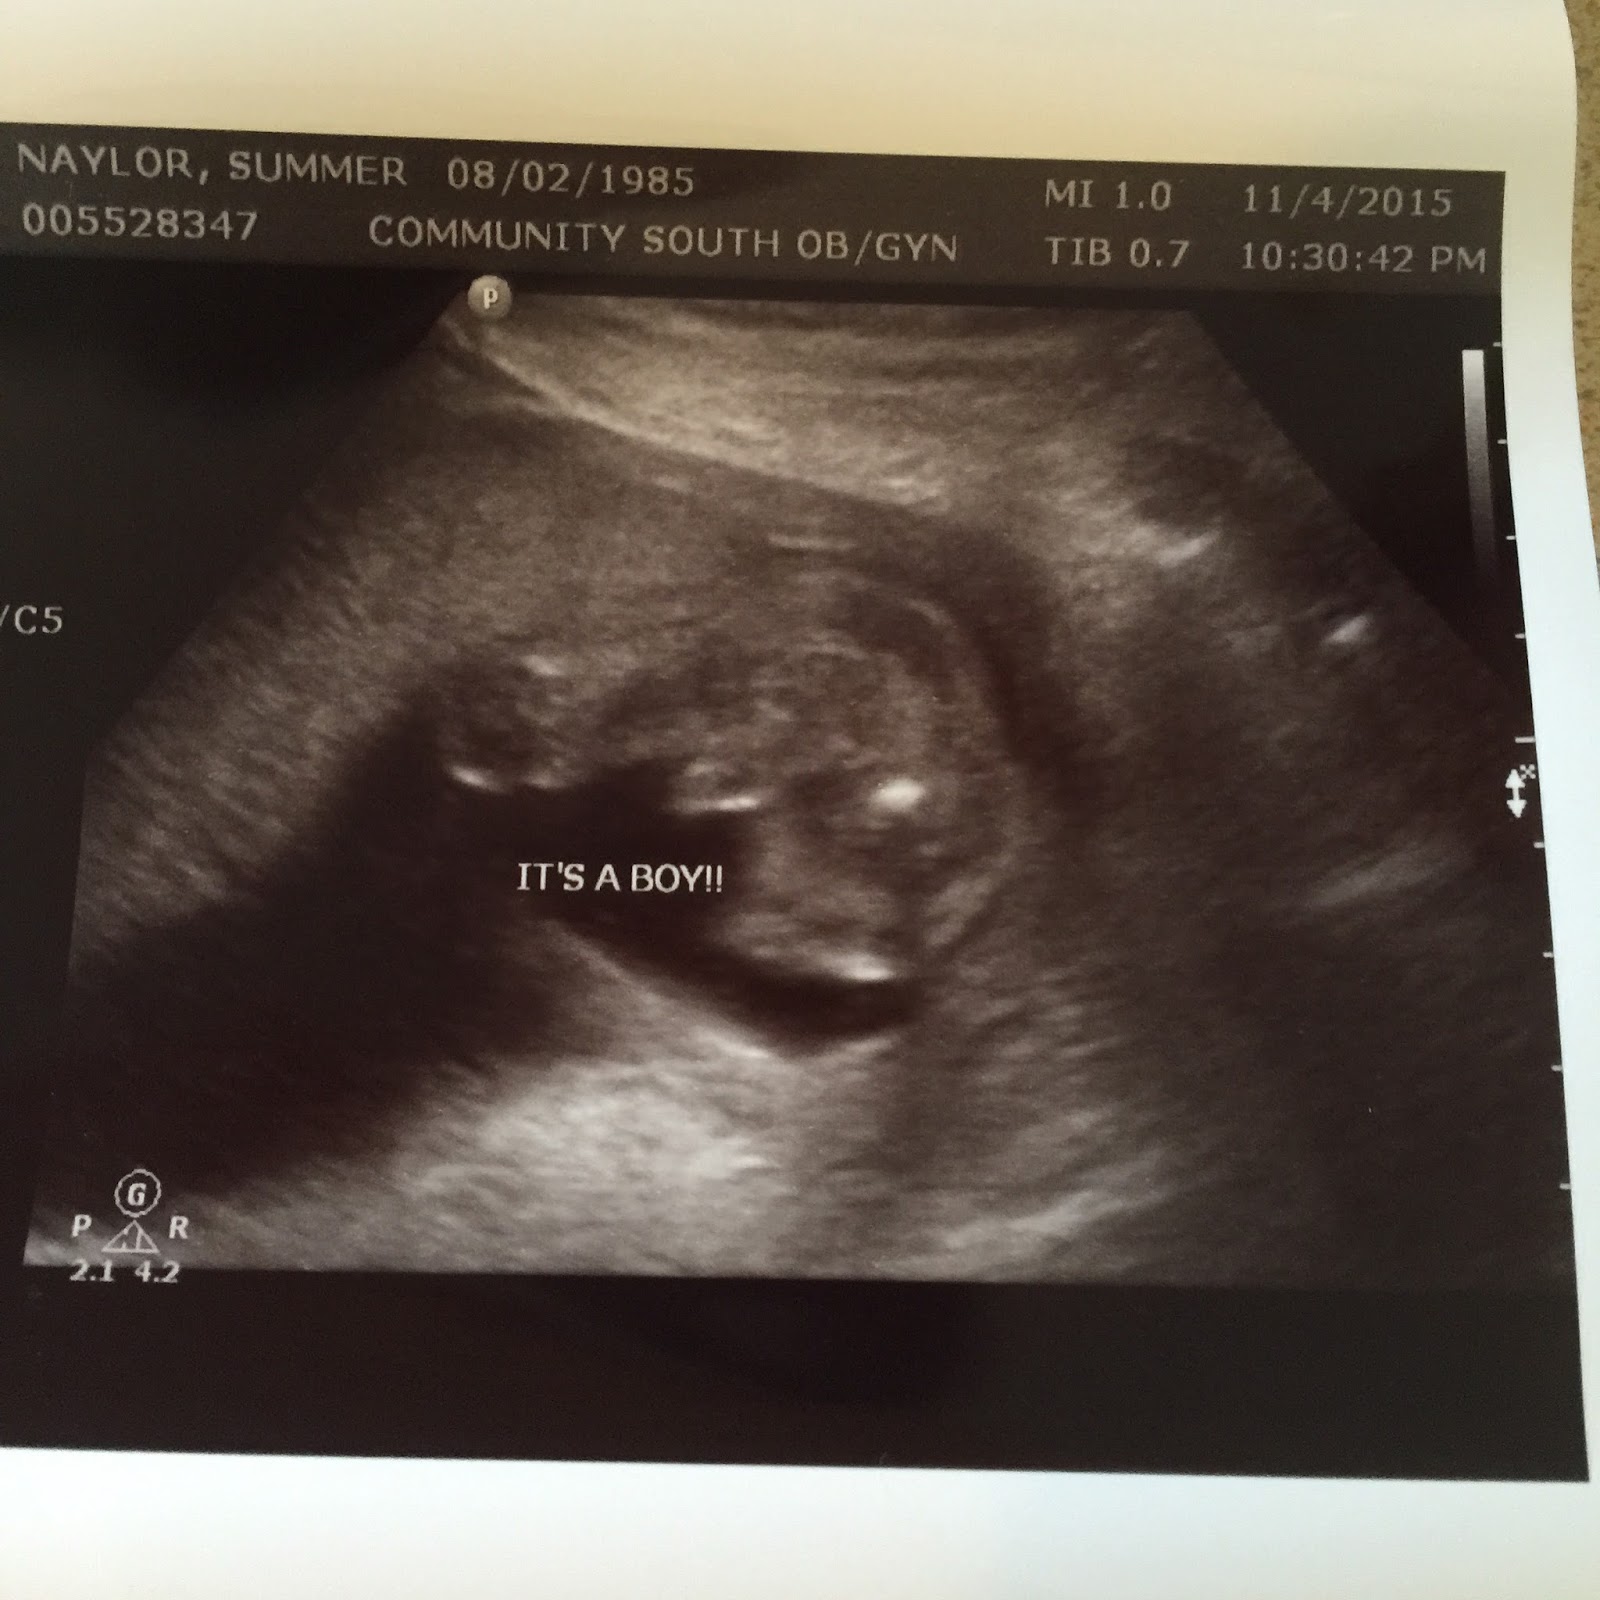

On Wednesday, the 4th Brian and I were able to go to my ultrasound appointment where we discovered (very obviously) that we are expecting another boy! We weren't too surprised, but it still took me a minute to wrap my mind around having a house full of boys and how outnumbered Maybrie and I will be. Growing up with so many sisters I feel like I don't know much about boys. Apparently the Lord plans to qualify and teach me through them. Thomas wanted a "grill" because we already have a boy baby- Ezra, but he is so carefree he is happy to have another brother. We told the kids as soon as Maybrie got home from school. Thomas had just been woken from a nap (which he rarely wakes happily from) and we dumped blue balloons on them from upstairs. Maybrie excitedly shouted "We're having a boy!" while jumping up and down while Thomas ran away crying... not because he was upset about the gender, but because he wanted balloons with pictures on them! haha Soon all three kids were happily playing with the dozen balloons. Maybrie is excited to be the only girl since she will always get her own room and be the favorite sister/daughter! We are all looking forward to his arrival and feel grateful that he is healthy and will be joining our family soon.